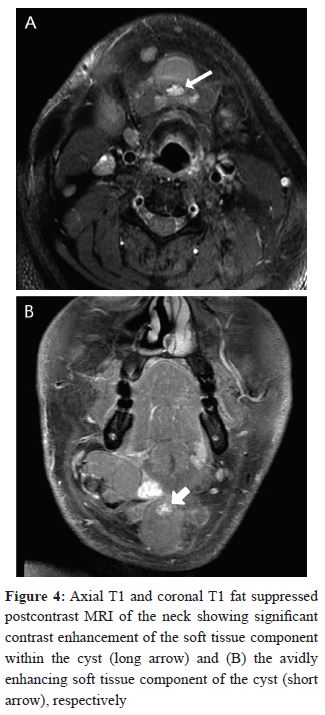

A solid enhancing mural nodule with calcifications was observed as well (Figure 4). Another lesion was noted in the right submandibular region measuring 4 × 3 cm indenting the ipsilateral submandibular gland, however no gross infiltration of the gland was seen. This was most likely anenlarged metastatic lymph node. Multiple suspiciouslevel II and III lymph nodes were also observed.The thyroid gland was normal with no focal lesions identified.